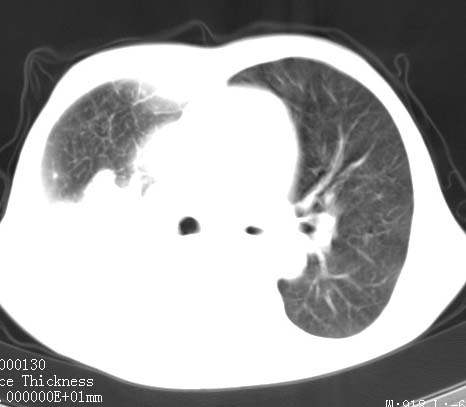

病人女 60岁 咳嗽 气促十余天,大叶性肺炎.

右肺上下叶均见 大片状密度增高影,边界清晰,其内可见支气管充气征,气管支气管通畅。纵膈略向右移位,其内无肿大淋巴结影。首先考虑炎性病变。不排除一些特异性的炎症。不知道发烧吗??wbc高吗??建议治疗后复查!!